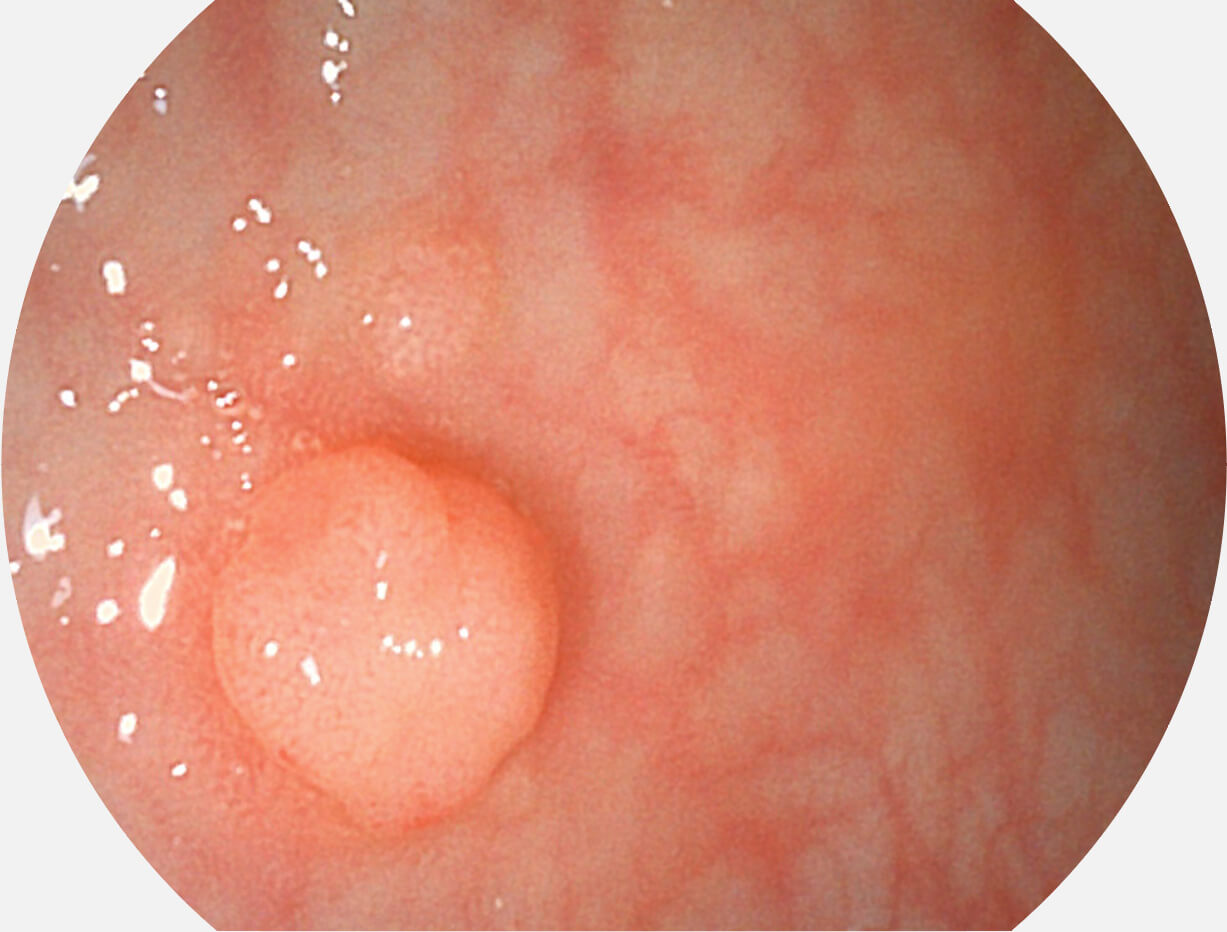

白光图像

SFI图像

Spectral Focused lmaging, SFI

图像具有高亮度、高黏膜血管颜色对比度的特点,且不改变粘液、食物残渣、粪便的基本颜色,可在中远景下进行观察,助力消化道早期疾病的诊断。